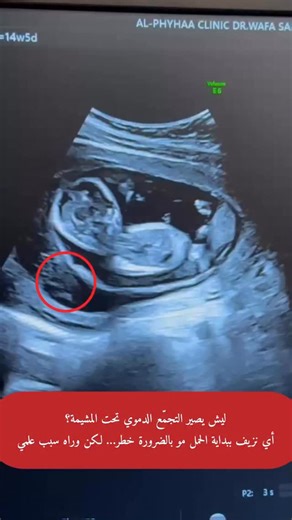

of the Right Flank - Subchorionic Hematoma

Pregnancy - Hematoma

Relief - Subchorionic Hematoma

11 Weeks - Subchorionic